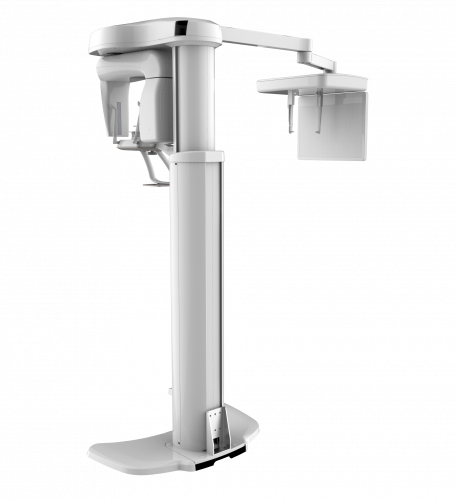

The PaX-i provides precise high-quality panoramic image by combining image processing and accumulated experience in dental imaging from VATECH. This will improve your diagnostic accuracy by increasing treatment planning and patient satisfaction.

A clear and sharp panoramic image brings you better diagnostics.

Advanced details, especially in the anterior and roots, can easily be viewed with the PaX-i.

These consistently high-quality images are the new standard of panoramic imaging.

| TYPE | TOP VIEW | FRONT VIEW |

|---|---|---|

|

PaX-i (Pano) |

|

|

|

PaX-i SC (Pano/Scan Ceph) |

|

|